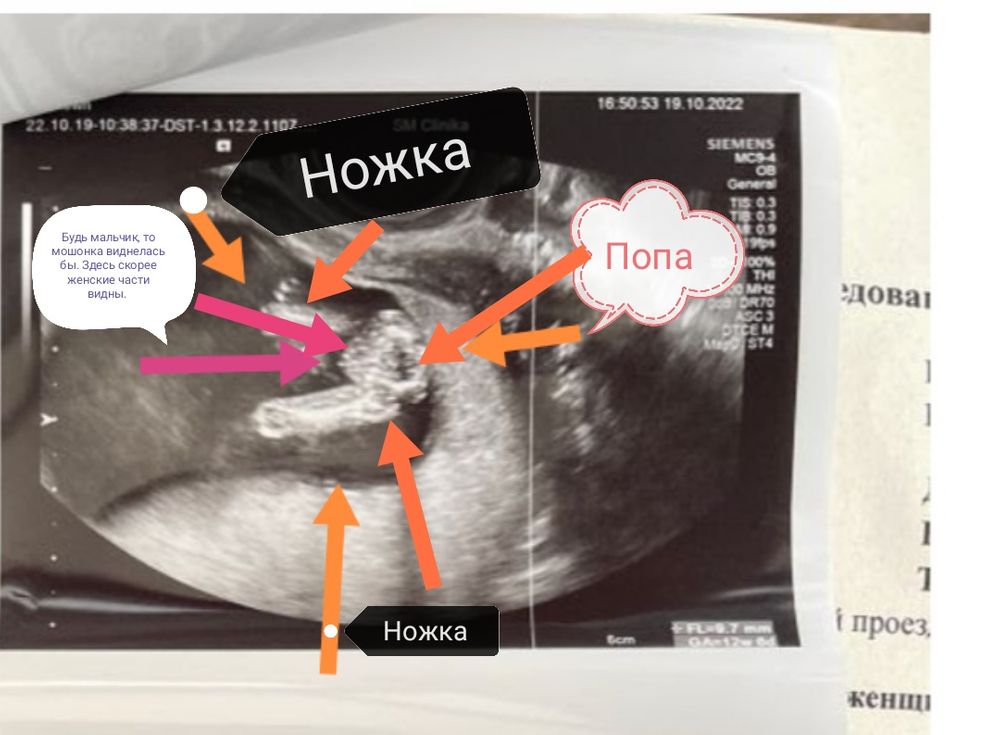

Девочки, как думаете это девочка или мальчик?

пол не предположили.

Но интерес берет своё, вот думаем гадаем )

По такой фотографии точно не скажешь. Нужен снимок сзади, снизу - с видом попы

Polina Dyakova, 95%,что и девочка.

5 % - ну оооочень стеснительный мальчик, который спрятал свои прелести.

Половой бугорок не видно, так что пол не предположить. Лобик на мальчуковый похож, но это как на кофейный гуще гадать)

По-моему , здесь не видно полового бугорка , а значит и пол предположить невозможно ))

Сходила на платное узи сегодня )